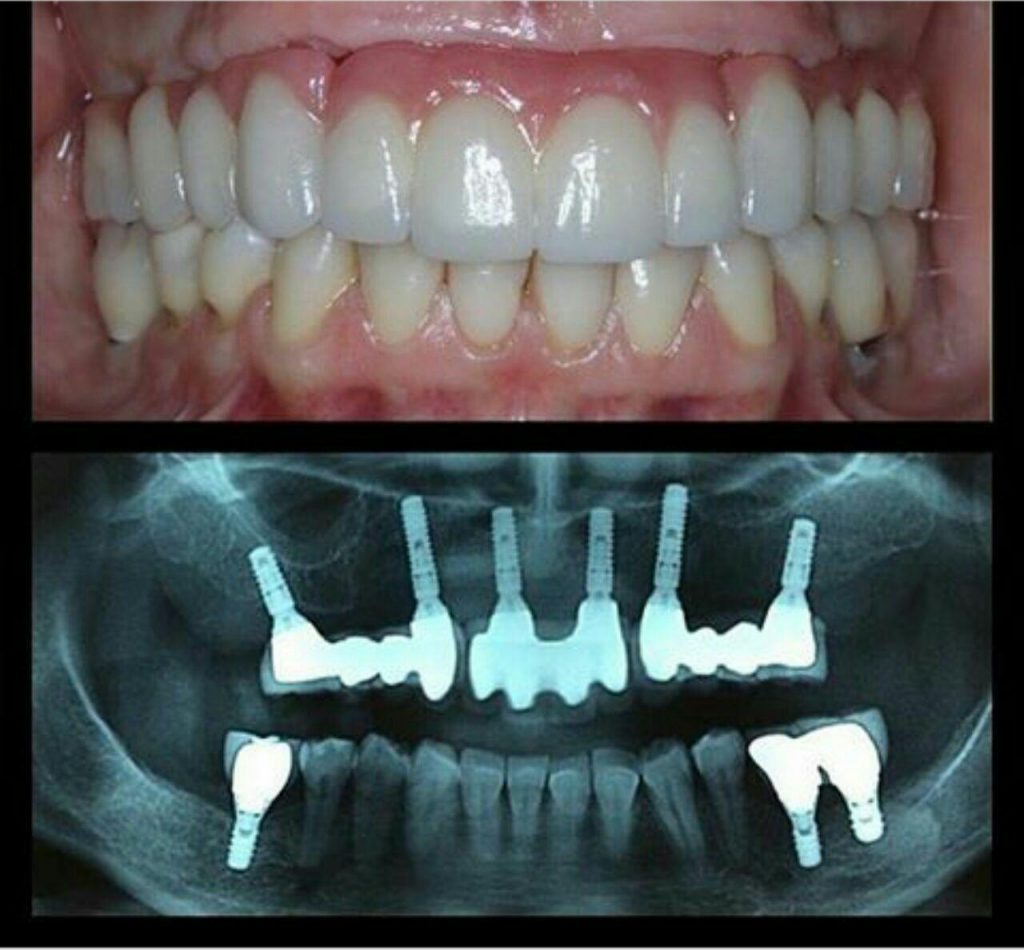

كلينيك تخصصي دندانپزشكي دكتر حامد كرامت

جراح دندانپزشك

فلوشيپ ايمپلنت از ICOI آمريكا

گواهينامه ايمپلنت و زيبايي از دانشگاه UCLA آمريكا